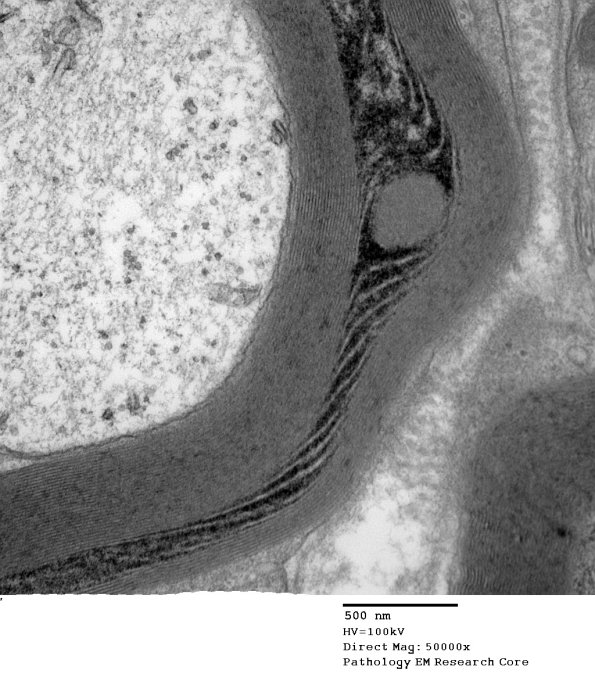

Washington University Experience | PERIPHERAL NEUROPATHY | 3 NORMAL MYELIN & SCHWANN CELLS | 3 Schmidt-Lanterman Clefts | 10C3 SLC (Case 10) EM 164 - Copy

Higher magnification of image #10C1. (electron micrograph)